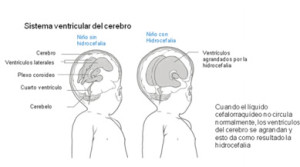

Hidrocefalia

La acumulación del líquido cefaloraquídeo puede producir presión e inflamación en el cerebro.

En el 80 por ciento de las personas afectadas por espina bífida, la hidrocefalia sólo se puede tratar insertando un tubo de drenaje llamado “derivación de líquido cefalorraquídeo”.

No existen medicamentos que puedan tratar la hidrocefalia con eficacia. La derivación se coloca debajo de la piel desde la cabeza (ventrículos) hasta la cavidad abdominal, donde el líquido cefalorraquídeo es rápidamente reabsorbido por el cuerpo.

Las derivaciones no son una solución perfecta para el tratamiento de la hidrocefalia, ya que pueden romperse, taparse o infectarse y a veces es necesario reemplazarlas a medida que el niño crece o cuando la derivación falla.

En la mayoría de los casos las derivaciones son necesarias durante toda la vida.